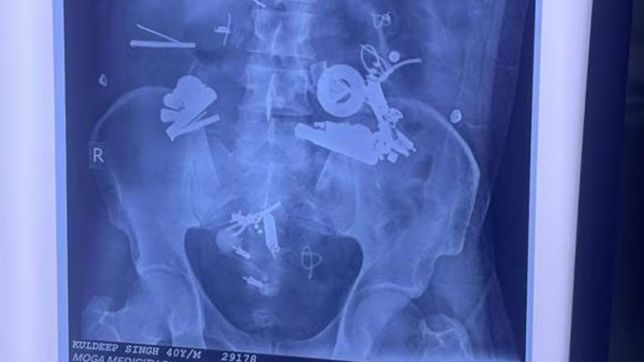

Fones de ouvido, medalhões, parafusos, alfinetes, botões de camisa e zíperes são alguns dos objetos removidos do estômago de um homem de 40 anos após uma cirurgia de três horas no hospital Medicity, em Moga, Punjab, na Índia, na última quinta (28/9).

Segundo o jornal indiano The Hindustan Times, o paciente, Kuldeep Singh, foi internado no hospital após apresentar febre alta e dores de estômago e reclamar de náuseas por mais de dois dias. Quando os médicos realizaram uma radiografia para determinar a causa dos problemas, ficaram chocados.

O exame mostrou vários objetos metálicos alojados dentro do estômago do indiano. Por meio da demorada cirurgia, a equipe médica conseguiu remover com sucesso os itens.

Imagens dos itens removidos do estômago de Kuldeep Singh começaram a circular nas redes sociais e, claro, viralizaram.

Citado pelo jornal, o diretor do hospital Medicity, Ajmer Singh Kalra, disse que o paciente sofria de dores de estômago há dois anos. “Ao fazer uma radiografia, encontramos medalhões, correntes, porcas, parafusos, fones de ouvido e muitos outros objetos dentro do estômago. Decidimos então operá-lo”, comenta o especialista.

Ao The Hindustan Times, Kalra disse que esse foi o primeiro caso do tipo em toda sua carreira. Apesar do sucesso no procedimento cirúrgico, o médico explicou que, como os objetos ficaram muito tempo no estômago, o estado do paciente ainda não era estável.

Fones de ouvido, medalhões, parafusos e até zíperes estavam

dentro do estômago do indiano (Foto: Ajemr Kalra/

Moga Hospital/Divulgação)

Os familiares de Singh também ficaram surpresos com o raio-x e os itens descobertos dentro dele e não tinham ideia de como conseguiu ingerir tudo isso. De acordo com os familiares, o indiano reclamava de dor de estômago e não conseguia dormir. “Depois que os sintomas pioraram e ele não conseguia nem dormir, procuramos os médicos”, disse um dos parentes, que confirmaram ainda que Kuldeep Singh sofre de problemas mentais.